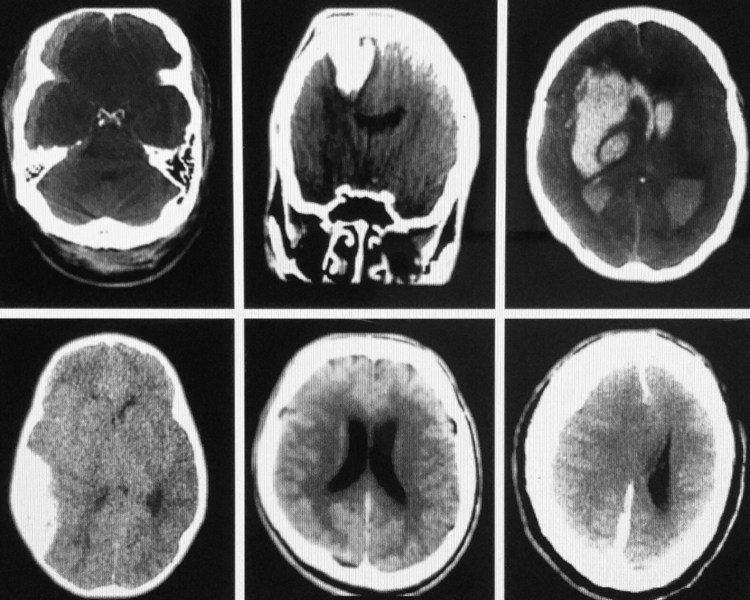

What is the diagnosis in each of these six patients? Assume they all arrive at the same time, i.e., this is a mass casualty event – How would you prioritize the overall management and transfer of any of these patients to a neurosurgeon?

In this group the lower middle slice is of a patient who would likely arrive dead: he has a massive SAH that surrounds all of the cortical surfaces/even extends a long the falx in the midline [appears fuzzy due to blood filling the subarachnoid spaces immediately adjacent to the cortical sulci and gyri. The ventricles are dilated due to blood causing a CSF convexity block. So you can’t save him. The arachnoid granulations are all blocked…CSF can’t exit the head so the ICP is markedly elevated. In the midline [along the falx cerebrii] the blood appears fuzzy because it is a thin film that follows the sulci/gyri closely…it often looks like a zipper…described as the “zipper sign” and proves its a SAH along both sides of the falx. No intervention for this patient.

Next, the patient in the upper middle slice has a knife blade penetrating into the brain: traumatic penetration by knife [knife not visible on this slice] requires immediate transfer [1st] especially if no other injury. The knife should not be removed in the ED.

The upper left slice is of a patient with the lowest acuity [a right frontotemporal SDH [venous bleeding] and could be transferred last in this mass casualty simulation. However, this patient requires RSI before transfer. This patient has has midline extension and a collapsed ventricle [mass effect] which should improve w/measures to lower the ICP…treat and transfer simultaneously [urgently].

An acute epidural hematoma is due to arterial hemorrhage [lens-shape-lower left slice and generally more acute than a SDH]. The issue…if hemodynamically normal with reactive pupils [intubate/mild hyperventilation after RSI [all get RSI except the SAH…he is dead]. An EDH might even require an emergency burrhole if the patient decompensates in the ED.

Next, a patient with a hypertensive bleed [upper right slice] requires mild hypervent/transfer ASAP & might survive, but the prognosis is poor. Decades prior if there was intraventricular blood most had very low survival…this is a patient with a right-sided AVM that ruptured [comorbidity: chronic hypertension]. The danger is the BP…do not lower the BP because with chronic hypertension cerebral perfusion is reset to a higher range to maintain cerebral blood flow; it is best to gently do RSI and transfer; this patient actually survived [as did all but the patient with the massive SAH].